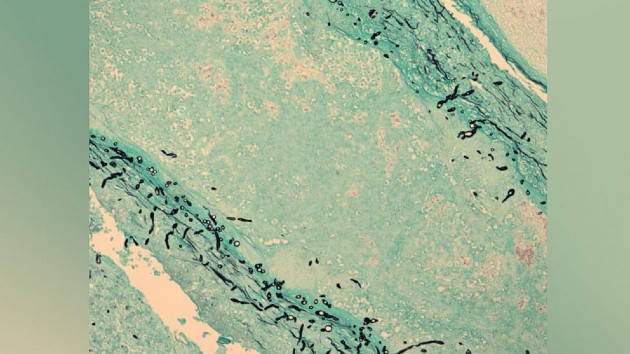

Meningitis is a type of infection and inflammation affecting the fluid and three meninges — or membranes — that protect the brain and spinal cord.

Fungal meningitis specifically occurs after someone contracts a fungal infection that spreads to the brain or spinal cord, according to the CDC.

Many fungi are too small to see with the naked eye so it’s easy for people to breathe in or ingest microscopic spores, the CDC says.

To be diagnosed with fungal meningitis, a patient gives samples of blood or cerebrospinal fluid that are tested for the presence of fungi.